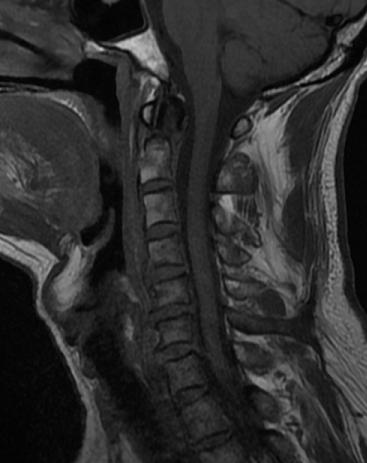

近日,45岁的王先生因高处坠落伤致颈部疼痛、活动受限,于是到北京友谊医院就诊。结合CT结果,医生诊断王先生为枢椎齿状突II型骨折,需手术治疗,王先生被收入骨科病房。

辅助检查显示:颈椎前部可及多发血肿,枢椎齿状突骨折部位向后方移位。

骨科主任医师唐海、单建林两位专家分析患者病情认为,王先生为枢椎齿状突的血运呈双侧雨刷状分布,保守治疗骨折不愈合的风险极大。行内固定手术无疑是最佳的选择,但是手术部位高位颈髓是生命中枢,手术难度极大,对术者的操作要求较高,如有不慎,会给患者带来灾难性后果。经过仔细地考虑,唐海与单建林为患者制定了详细的手术计划,决定实施枢椎齿状突骨折内固定手术。